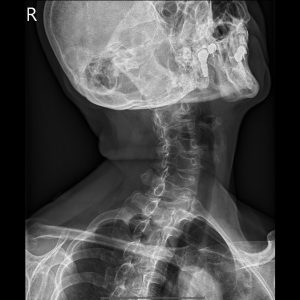

C spine Lat view

C1 & C2 ( Open Mouth )

C spine Extension view

C spine Flexion view

C-spine Oblique view(RPO)

C-spine Oblique view(LPO)